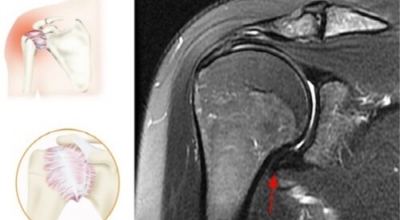

오십견이란?

만성 어깨관절의 통증과 운동제한을 유발하는 가장 흔한 질환의 하나로 전체 인구의 약 2%에서 유발돼요. 동결견이라 하며 흔하게 50세 이후 특별한 원인 없이 심한 통증과 더불어 전 방향으로 능동적, 수동적 관절 운동 범위의 제한을 관찰되는 것이 특징이지요. 꼭 50대에만 발생되는 것이 아니며, 젊은 연령대나 50대 이후에도 발생할 수 있어요.